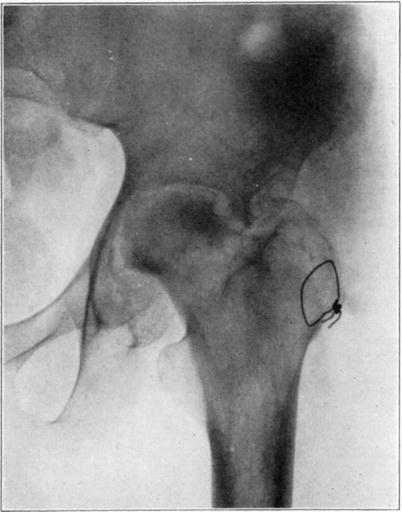

Operations which involve severence of bone or extensive separation of soft parts from bone may occasionally interfere with blood supply sufficiently to cause massive necrosis. An example of this is the necrosis of the head and neck of the femur in the following case in which arthroplasty of the hip was performed.

Case 1. Bony ankylosis following pyogenic arthritis.

Case 1. Twenty days after arthroplasty.

Case 1. Thirty-six days after arthroplasty. Beginning reduction in density in base of neck and shaft. No change in head.

Case 1. One hundred and fifty-one days after operation. Density of necrotic head unchanged but shaft and pelvis show atrophy of disuse.

Case 1. Two hundred and fifty days after operation. Head extensively reduced in density from invasion and replacement from the living bone of base of neck.

Case 1. Four hundred and four days postoperative Cavitation at base of head and further transformation.

The hip showed about forty degrees of flexion but marked limitation of abduction and rotation. Its strength had gradually improved and there was only slight discomfort in walking unless it was prolonged.

The cause for this exceptional occurrence of necrosis of head and neck without sequestration appeared to lie in the traumatism of head and denudation of neck of its covering of soft parts. However, it may have been due in part to deep-seated mild infection in the region of the new joint, despite the absence of discharge from that region. Failure of the necrotic head to be sequestrated speaks decidedly in favor of aseptic instead of septic necrosis although sequestration may not occur in the presence of mild infection of a necrotic area. In another case I observed necrosis of the head and neck following an arthroplasty in which there was infection of the wound with a purulent discharge, but the dead bone was sequestrated in the course of several weeks. In the case here reported functional stimulation of the bones resulting from movement of the joint, combined with protection of the necrotic head from weight-bearing, was followed by creeping substitution of the necrotic bone by new bone in the greater part of the head without either erosion of dead bone or the development of marked deformity.